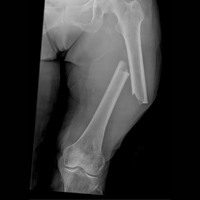

Незважаючи на те що проблема не нова, травматизм залишається однією з актуальних проблем сучасної медицини, оскільки серед постраждалих із травмами відзначаються високі рівні інвалідизації та смертності. Традиційний погляд на травми як на нещасні випадки або як на випадкові події призвів до деякої зневаги в цій галузі суспільної охорони здоров’я. Однак останні оцінки показують, що травми є однією з головних причин смерті та інвалідності у світі. Вони зачіпають все населення, незалежно від віку, статі, доходу або географії регіону. Травми, за даними Всесвітньої організації охорони здоров’я (ВООЗ), є причиною 16% глобального тягаря хвороб і призводять до 5,8 млн смертей щорічно.

Україна займає перше місце за смертністю в Європі. У країні щорічно травми різної тяжкості отримують понад 4,5 млн людей, летальність внаслідок травм в останні роки має стійку тенденцію до зростання.

Травматизм в Україні — головна причина смерті найбільш працездатного населення України віком до 40 років. Травматизм необхідно розглядати як пріоритетне питання у здоров’ї нації та практично як загрозу національній безпеці. Вже немає сумнівів, що сьогодні для всього цивілізованого суспільства тяжка травма є «Вбивцею № 1», оскільки гине переважно молода і працездатна частина населення.

Особливу увагу учасники круглого столу приділили питанню сучасної бойової травми та участі медичних закладів Міноборони, МОЗ та НАМН України у системі надання високоспеціалізованої медичної допомоги постраждалим в умовах проведення АТО.